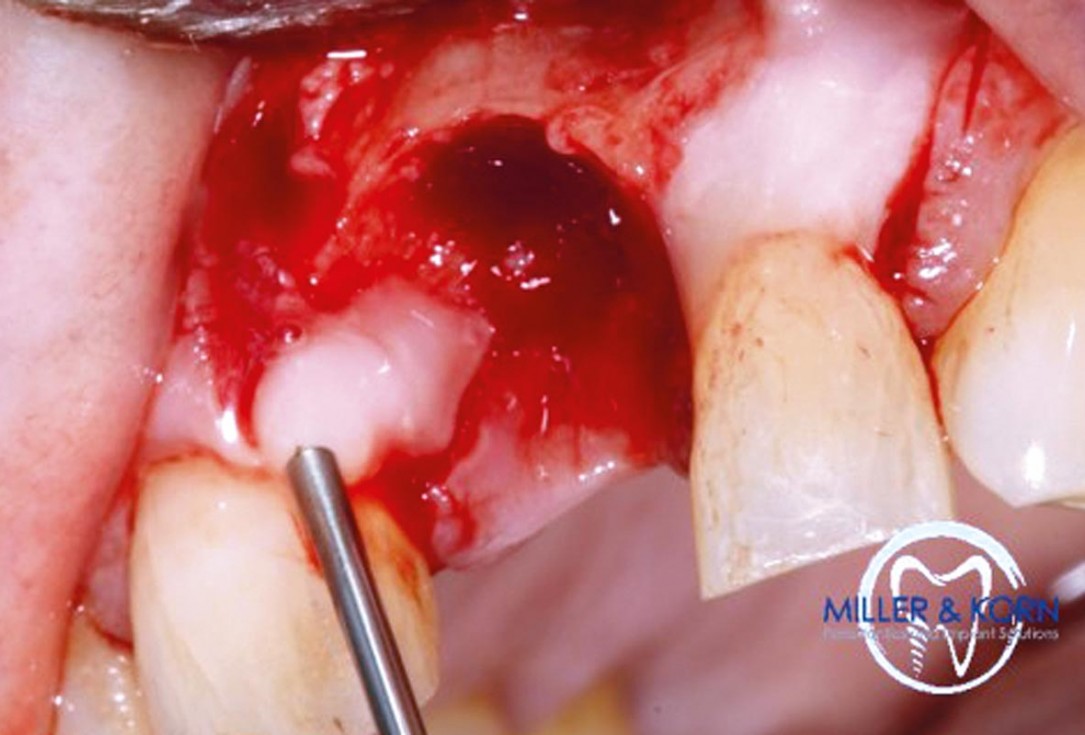

04/39 - Preparation of a full thickness flap and careful debridementImmediate implant placement and correction of horizontal and vertical bone loss using an allograft bone ring, cerabone® and Jason® membrane - Drs. Miller and Korn